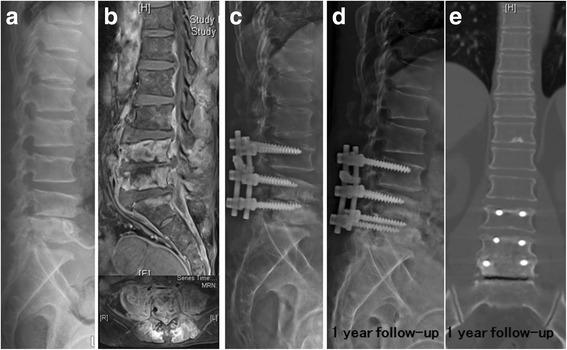

From January 2003 to January 2013, 54 patients who underwent combined antibiotic and surgical therapy in the treatment of hematogenous pyogenic spondylodiscitis were included.

Compared with 37 GPC-HPS patients, the 17 GNB-HPS patients were more often found to be older individuals, a history of cancer, and a previous history of symptomatic urinary tract infection. They also had a less incidence of epidural abscess formation compared with GPC-HPS patients from findings on magnetic resonance imaging (MRI). Constitutional symptoms were the primary reasons for initial physician visits in GNB-HPS patients whereas pain in the affected spinal region was the most common manifestation in GPC-HPS patients at initial visit. The clinical outcomes of GNB-HPS patients under combined surgical and antibiotic treatment were not different from those of GPC-HPS patients. In multivariate analysis, independent predicting risk factors for GNB-HPS included a malignant history and constitutional symptoms and that for GPC-HPS was epidural abscess.

与37例GPC-HPS患者相比,17例GNB-HPS患者年龄更大、更多有癌症病史及既往有症状性尿路感染史。磁共振成像(MRI)结果显示,与GPC-HPS患者相比,他们硬膜外脓肿形成的发生率更低。全身症状是GNB-HPS患者初次就诊的主要原因,而受累脊柱区域疼痛是GPC-HPS患者初次就诊时最常见的表现。联合手术及抗生素治疗的GNB-HPS患者的临床结局与GPC-HPS患者无异。多因素分析中,GNB-HPS的独立预测危险因素包括恶性病史和全身症状,GPC-HPS的独立预测危险因素是硬膜外脓肿。